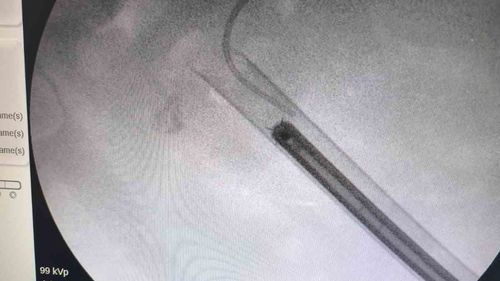

Siirt'te 34 yaşındaki Fatih Aslan'ın böbreğinde tespit edilen staghorn ('geyik boynuzu') taşı, PCNL yöntemiyle tek seansta yaklaşık 1,5 saatte temizlendi.

Siirt'te 'geyik boynuzu' böbrek taşı PCNL ile tek seansta temizlendiSiirt'te 34 yaşındaki Fatih Aslan, ateş, üşüme ve idrar yaparken yanma şikayetleriyle hastaneye başvurdu. Yapılan muayene ve testlerin ardından piyelonefrit (böbrek iltihabı) tanısı konuldu ve enfeksiyon tedavisi tamamlandı.Tanı ve görüntüleme bulgularıTanı…